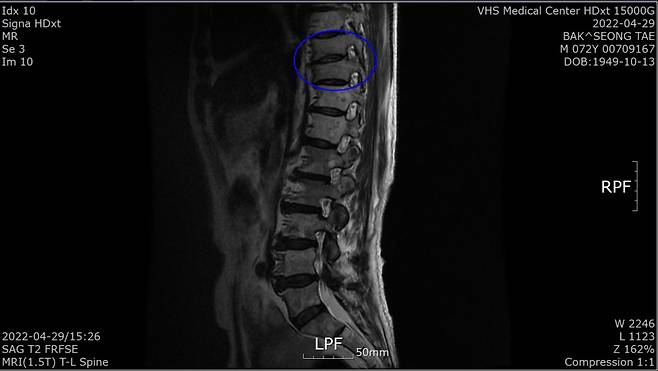

“1월 말 허리가 아파 병원에 갔더니 전립선암 말기라고 하더라고요. 전 베트남 참전용사로 국가유공자라 중앙보훈병원에서 진단 받았습니다. PSA(Prostate Specific Antigen·전립선 특이항원·전립선암의 선별검사 및 치료 판정을 위한 종양지표지자 검사)가 935 ng/mL라는 겁니다. PSA 4 ng/Ml 이하가 정상이라는데…. 너무 놀라서 그동안 아무 증상이 없었다고 했더니 전립선암은 증상이 없다 갑자기 나타난다고 하더군요. 전이가 돼 흉추 9, 10번이 시커멓게 썩었다고 하더군요. 참 나…. 방법이 죽을 방법 밖에 없다니. 하느님이 원망스러웠습니다.”

4월 29일 검사에서 PSA 수치가 0.059ng/mL로 떨어진 것이다. 그는 “MRI(자기공명촬영) 결과 새까맣던 흉추도 하얗게 정상으로 돌아왔다”고 했다. 말기암 판정 5개월여 뒤인 7월 29일 검사에선 PSA가 0.008 ng/mL로 떨어져 있었다.